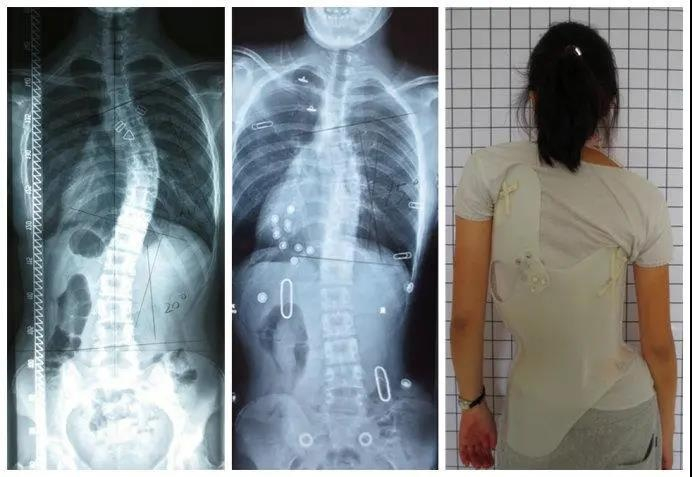

脊柱侧弯怎样治疗?

目前国际上公认的方法就是手术治疗和保守治疗,通常根据患者的年龄、性别、剩余生长潜力、躯干旋转角度及cobb角(脊柱侧弯严重程度的参考标准之一)的大小等因素来选择合适的治疗方案。